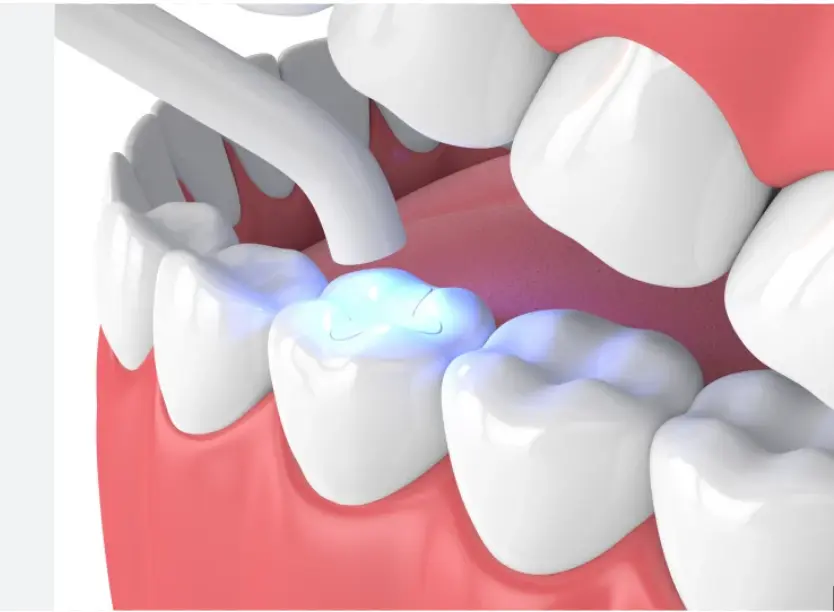

Dental Fillings

Tooth-colored composite fillings that blend seamlessly with your natural teeth